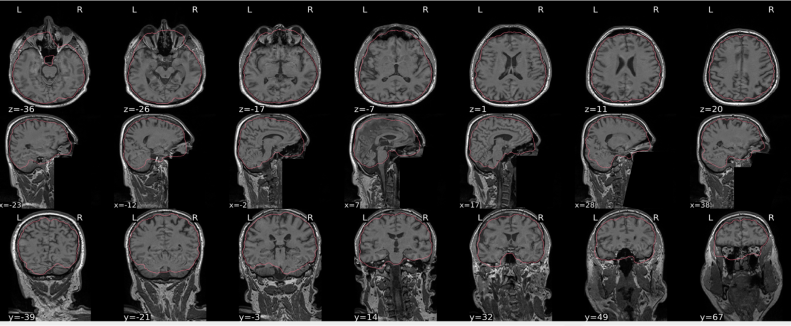

T1w skull stripping

Skull stripping is the process separating the brain (cortex and cerebellum) from the skull. The red line follows the outline of the brain and it separates it from the skull.

Example of a good subject

- There are no skull stripping errors, such as portions of the brain missing, or too much of the skull retained

- The red line follows the outline of the brain

Example of a bad subject

- There are skull stripping errors, such as portions of the brain missing, or too much of the skull retained

- NOTE: check all the images (slices) in the report. If only one image (slice) looks problematic, it is possible that the subject is okay and it is just a visual issue in that particular screenshot

Summary

| Good | Bad |

|---|---|

| The brain is fully inside the red line | Structures like the cranium or the eyes are inside the red line |

| No important brain structures are outside of the red line red line follows the natural outline of the brain | Important brain structures are missing inside of the red line |

-> if only one slice is problematic, it could be an issue related to the visual depiction of the data instead of an issue related to the test subject